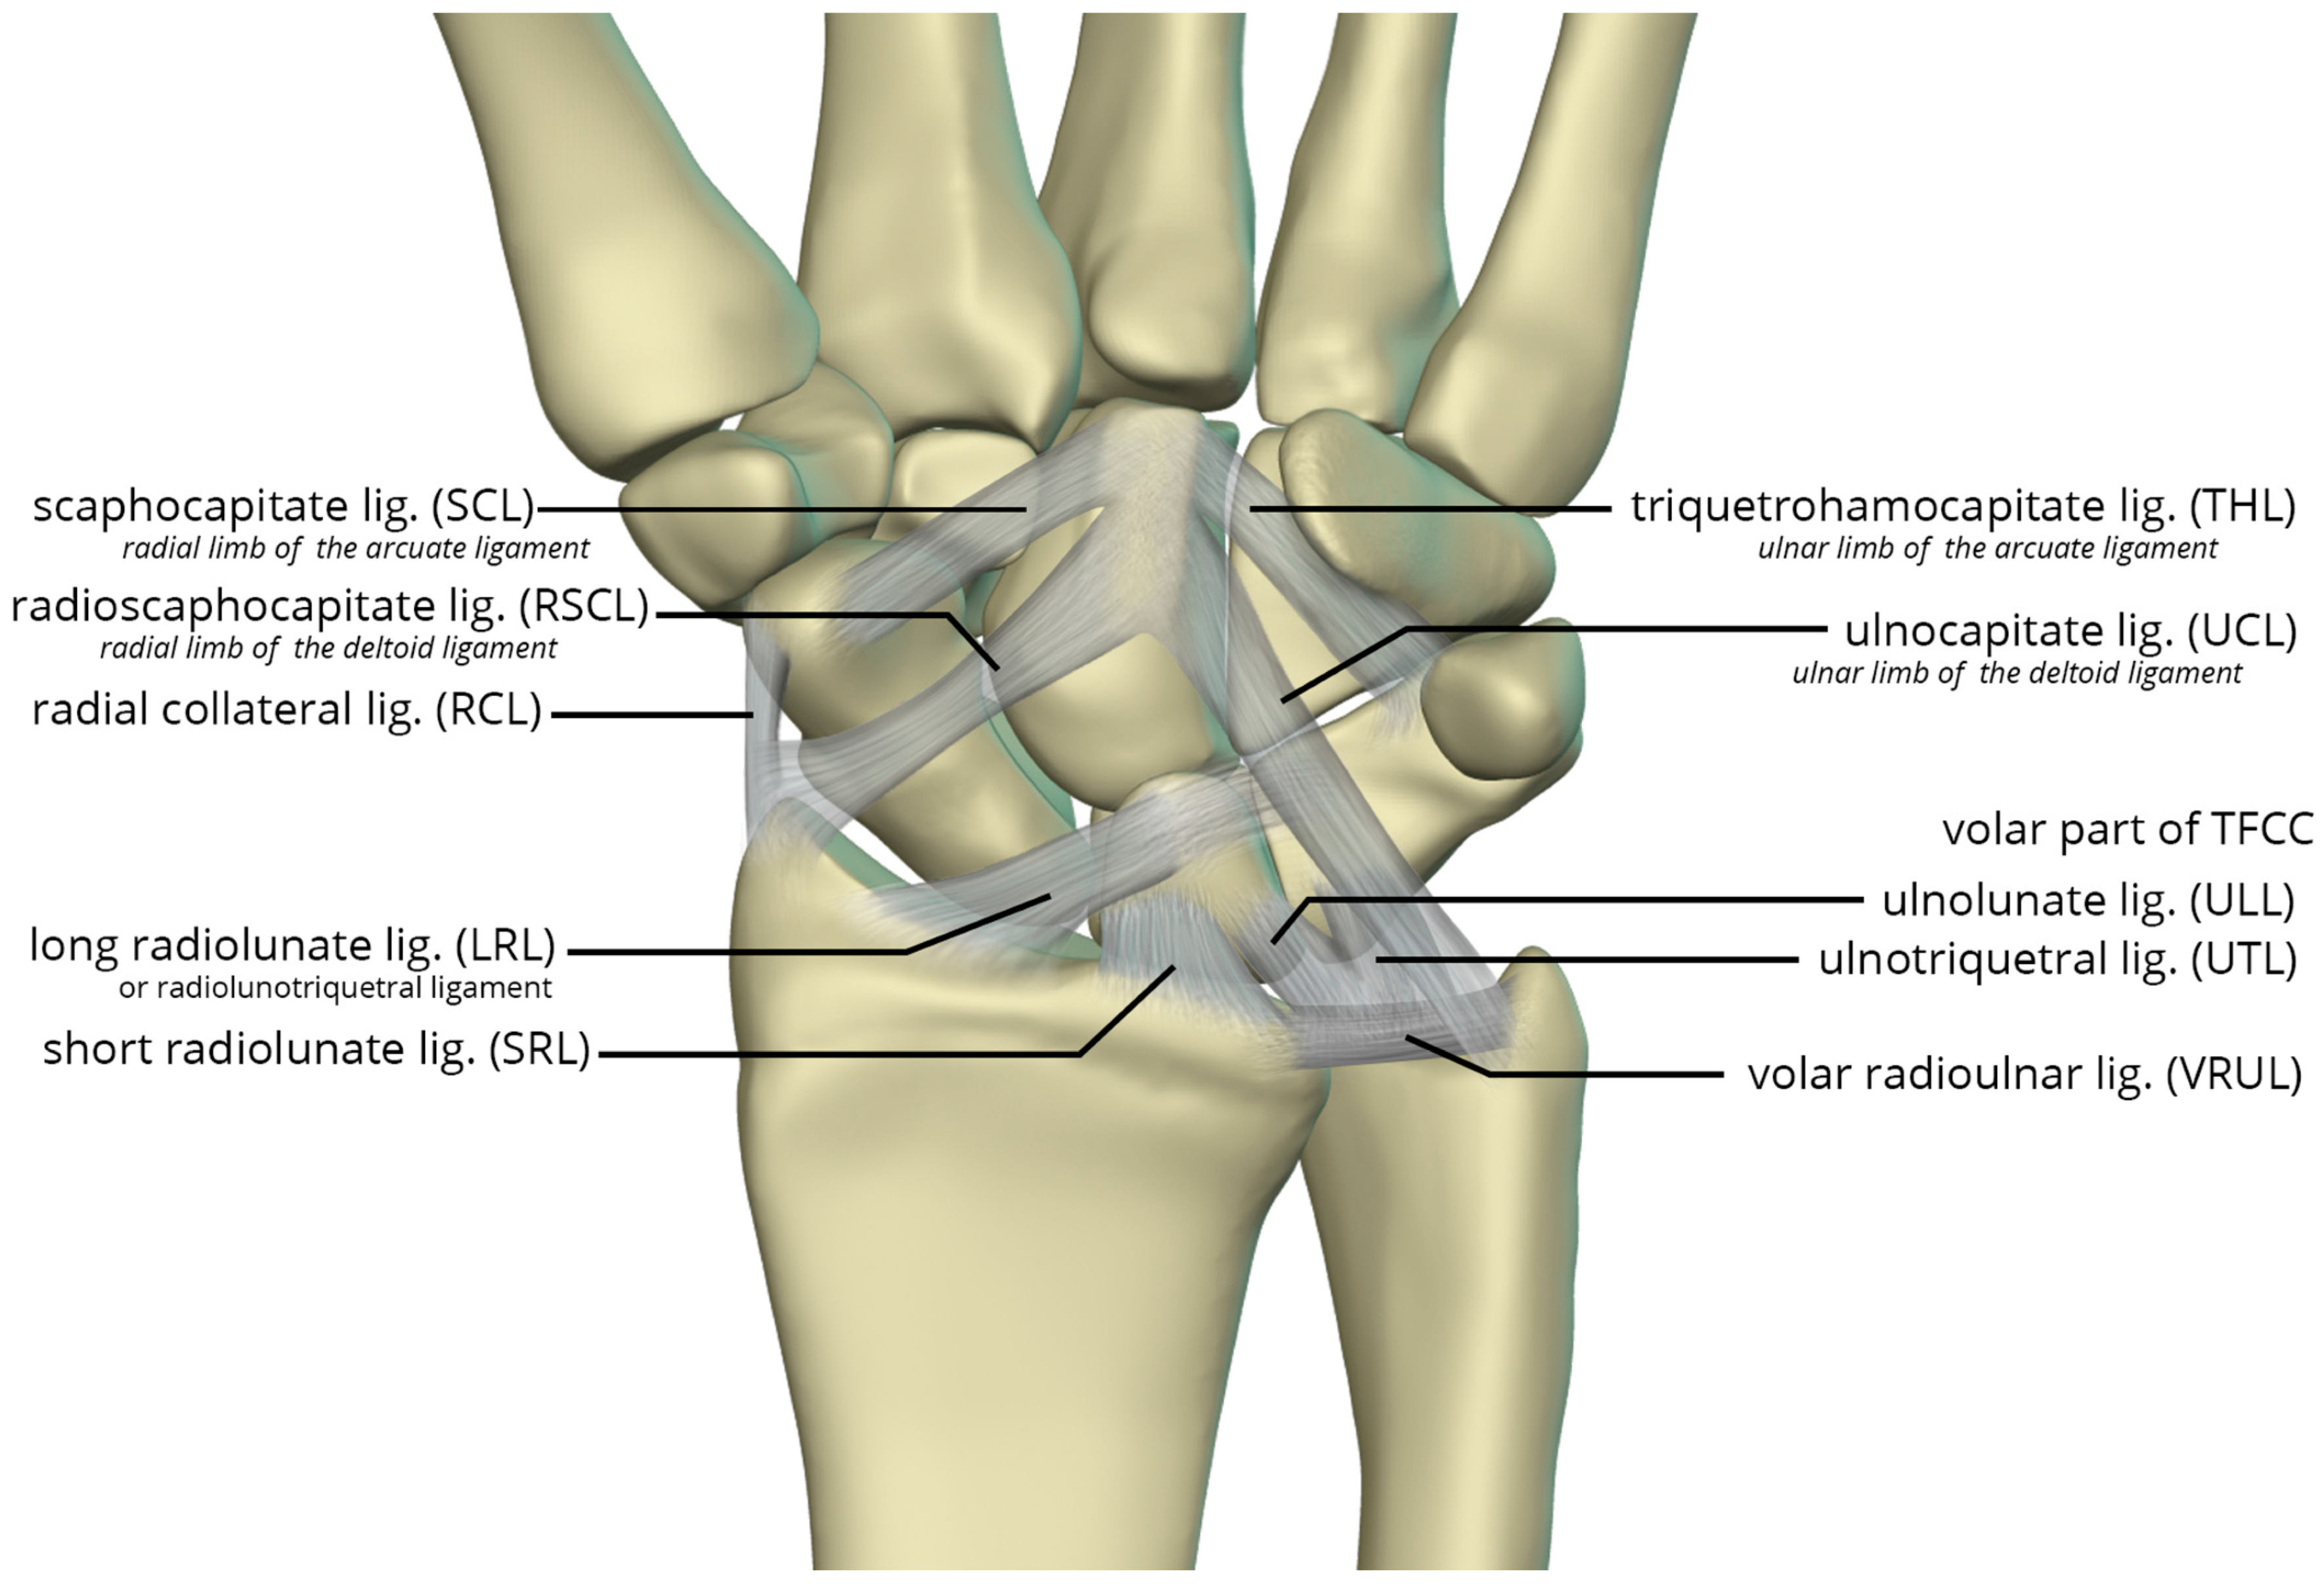

The volar radiocarpal ligaments include the radial collateral ligament (RCL), radioscaphocapitate ligament (RSCL), short radiolunate ligament (SRL), and long radiolunate ligament (LRL) (Figure 26). The RCL extends from the radial styloid to the scaphoid head. The RSCL arises from the radial half of the volar rim of the scaphoid fossa. The RSCL attaches to the capitate, forming a sling across the scaphoid. Some fibers may attach to the scaphoid. The SRL anchors the lunate from the radial half of the volar cortex of the lunate to the volar rim of the lunate fossa of the radius. The LRL arises from the volar aspect of the ulnar half of the scaphoid fossa rim of the radius. Distally, the LRL attaches to the volar aspect of the lunate, with some fibers also attaching to the volar triquetrum, and therefore may also be known as the radiolunotriquetral ligament.

The volar ulnocarpal ligaments (Figure 26) include the ulnolunate ligament (ULL), the ulnotriquetral ligament (UTL), and the ulnocapitate ligament (UCL) [25,26]. The ULL and UTL originate from the volar radiolunate ligament and attach distally to the volar surfaces of the lunate and the triquetrum, respectively. The UCL extends from the ulnar head to the capitate. The ULL and UTL, deeper to the UCL, is a single sheet of tissue arbitrarily divided according to their distal attachments.

Lastly, the volar midcarpal ligaments include the arcuate and deltoid ligaments that are further subdivided into radial and ulnar limbs. The scaphocapitate ligament (SCL) arises from the ulnar aspect of the distal pole of the scaphoid, deep to the RSCL, and extends to the volar capitate body. It represents the radial limb of the arcuate ligament. The triquetrohamocapitate ligament (THL) extends from the triquetrum to the capitate, across the hamate. It represents the ulnar limb of the arcuate ligament. Some describe this as the distal band of the palmar scaphotriquetral ligament, which is another mid-carpal capsular ligament superficial to the SCL and THL [26,27]. The distal RSCL represents the radial limb of the deltoid ligament, and the UCL constitutes the ulnar limb of the deltoid ligament, supporting the head of the capitate [27].

Figure 26. Illustration of the volar extrinsic carpal ligaments including the volar midcarpal ligaments, volar capsular ligaments, and volar ulnocarpal ligaments.